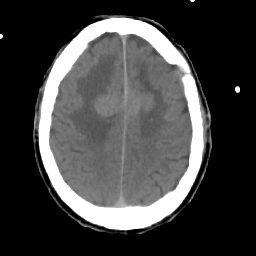

Meningioma: Roentgen-ray CT #2 -- Slice #15

[Home][Help][Clinical] Slice 15